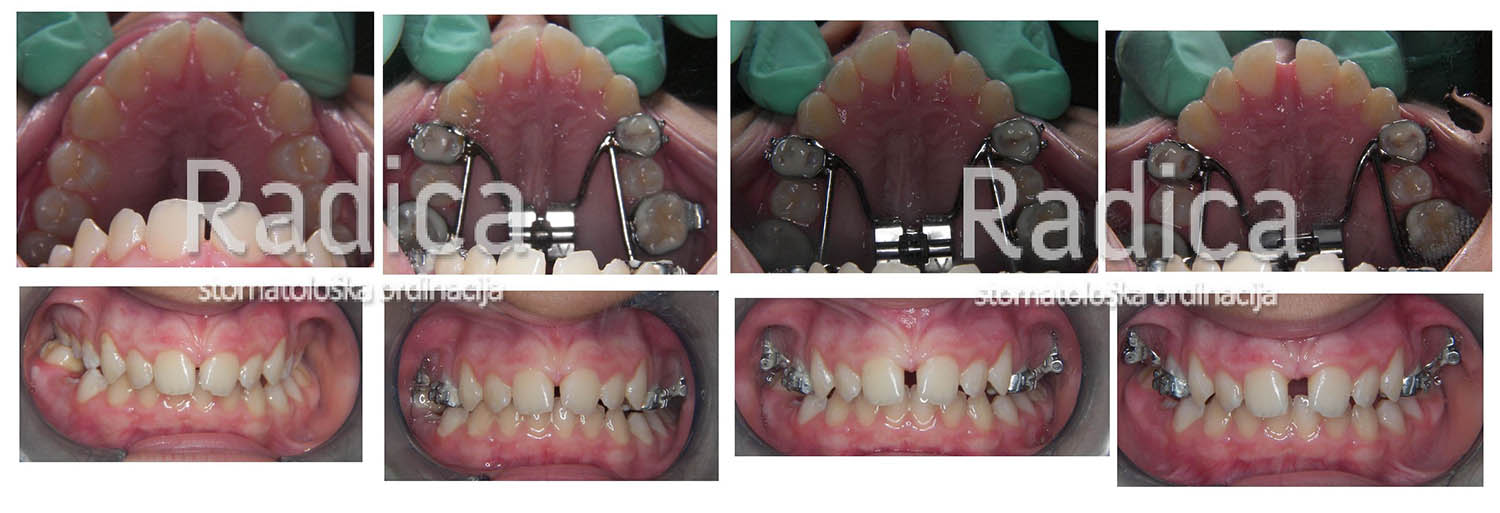

Hyrax se pomoću prstene fiksira na prve trajne molare i prve premolare. Vijak se okreće svaki dan i već nakon par dana se vidi učinak jer se pojavljuje razmak između sjekutića. Nakon dva tjedna se vijak blokira i aparat ostaje u ustima najmanje sljedećih 4-6 mjeseci. Fiksni aparat se obično stavi nakon tri mjeseca. Hyrax ima najbolji efekt u vrijeme mješovite denticije – najčešće između 9-12 godine.

U sljedećim galerijama možete vidjeti primjere upotrebe Hyraxa:

1. primjer

2. primjer